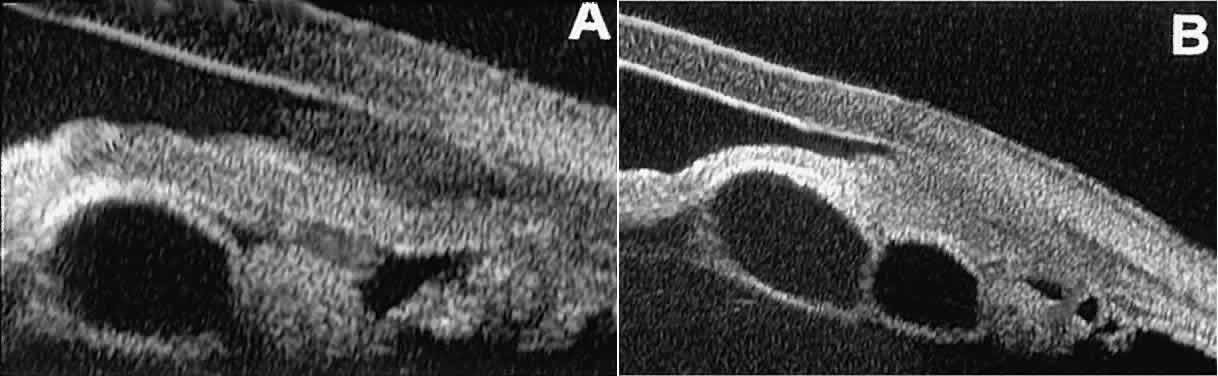

Solid iridociliary tumors present variable internal reflectivity depending

on tumor type.14 Most solid lesions that occur on the iris are nevi. Benign nevi of the

iris and ciliary body usually appear on UBM as relatively small hyporeflective

lesions replacing a part or all of the underlying uveal stroma

locally (Fig. 26). Such lesions usually do not destroy the underlying neuroepithelium of

the iris or ciliary body, extend intrasclerally, or have prominent intralesional

blood vessels.  Fig. 26. UBM features of iris nevi. A. Superficial nevus appears as hyper-reflective layer of iris (white arrow). Normal iris stroma (dark arrow) is more sonolucent. B. Fusiform nevus of peripheral iris occupying full thickness of iris stroma (arrow). Note intact iris pigment epithelium underlying lesion. Fig. 26. UBM features of iris nevi. A. Superficial nevus appears as hyper-reflective layer of iris (white arrow). Normal iris stroma (dark arrow) is more sonolucent. B. Fusiform nevus of peripheral iris occupying full thickness of iris stroma (arrow). Note intact iris pigment epithelium underlying lesion.

In contrast, malignant melanomas of the iris and ciliary body are much

less common. On UBM, such tumors are usually larger than benign nevi, and

they are more likely to have caused focal or extensive disruption

of the adjacent neuroepithelial layers, to have invaded the sclera, and

to be associated with prominent intralesional blood vessels (Fig. 27). Some malignant melanomas of the ciliary body and most ciliochoroidal

melanomas are too large in basal diameter to be fully revealed in a single

UBM image, and many of these lesions are also too thick to be measured

by this technology. In the case of a melanocytic tumor of the iris

or ciliary body that is not clearly either a benign nevus or a malignant

melanoma, serial UBM evaluations may prove useful for assessing

the tumor's growth and other changes that might warrant either biopsy

or complete excision of the mass.  Fig. 27. UBM features of malignant melanoma of iris. (A) Iridociliary melanoma replacing peripheral iris and ciliary body and filling

anterior chamber angle. Mass is slightly sonolucent compared with

normal iris stroma. (B) Larger iridociliary melanoma. Iris appears to arise from side of mass. Fig. 27. UBM features of malignant melanoma of iris. (A) Iridociliary melanoma replacing peripheral iris and ciliary body and filling

anterior chamber angle. Mass is slightly sonolucent compared with

normal iris stroma. (B) Larger iridociliary melanoma. Iris appears to arise from side of mass.

|